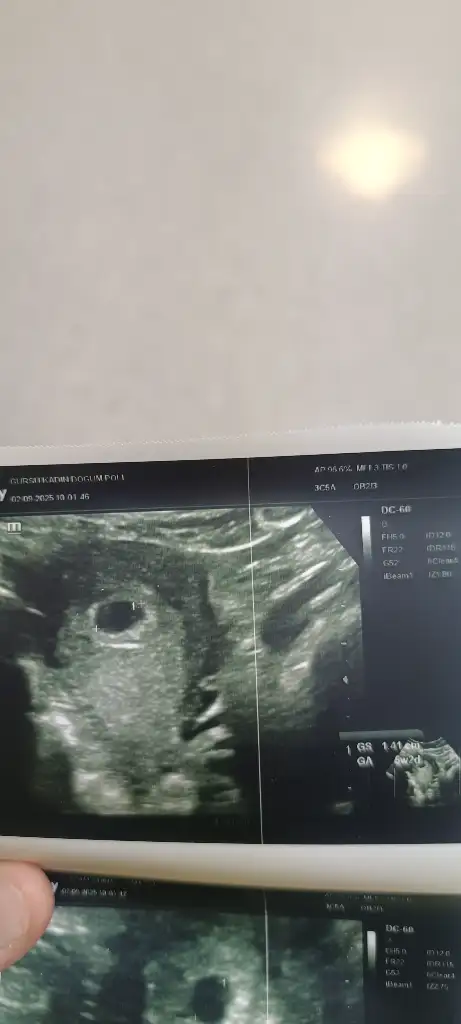

Sat la uyumlu muydu keseÇok güzelbende 4+5 de keseyi gördüm bi hafta sonra tekrar cagırdı duyar mıyım acaba kalbi zaman gecmiyor cuma günü gideceğim

Ben gecikmemden 13 gün sonra 23 değerle öğrendim 10 gün sonra kese gözüktü 4+5 dedi geç yumurtlamısım yani son adet tarihime göre 7 haftalık falan olması lazımdıSat la uyumlu muydu kese

Ben det gecikmesinden on gün sonra gitmiştim ilk kese ve yolc sac için. 5+5 kalp ıcn bana erken geldi ama yolc sacı ve bebegı görmek için cagırmıs olabilr yine erken